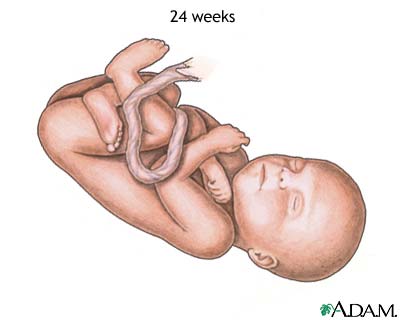

Week 22

- Lanugo hair covers baby's entire body.

- Meconium, your baby's first bowel movement, is made in the intestinal tract.

- Eyebrows and lashes appear.

- Your baby is more active with increased muscle development.

- The mother can feel the baby moving.

- Your baby's heartbeat can be heard with a stethoscope.

- Nails grow to the end of your baby's fingers.

Weeks 23 to 25

- Bone marrow begins to make blood cells.

- The lower airways of the baby's lungs develop.

- Your baby begins to store fat.